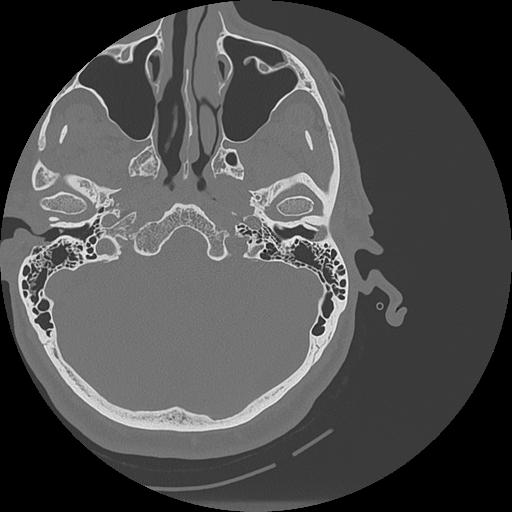

7 HUESO,,Vol,0.5,HUESO,,